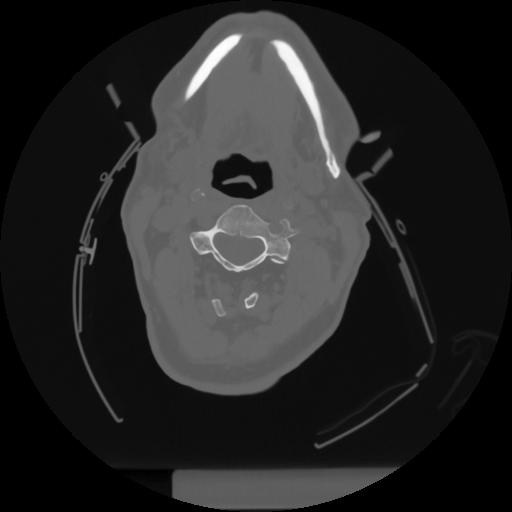

12 P.BLANDAS,,Vol,0.5,P.BLANDAS,,